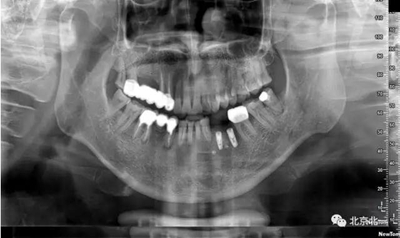

患者術(shù)前片, 最窄骨寬度僅僅3mm,34-35牙位缺失,